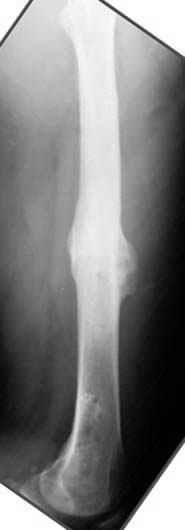

На рисунке N1 предоперационный план лечения ложного сустава шейки бедра- линия ложного сустава, угол и направление введения импланта, клиновидная остеотомия в градусах и миллиметрах, второй снимок после коррекции, расчет, на сколько удлиняется конечность и размеры импланта;

N3 рисунок окончательный снимок, после операции моя рентгенограмма должен выглядеть примерно как эта картина. На N4 снимке клин перед удалением; N5 послеоперации 3 нед.; N6 окончательная рентгенограмма.

Отправитель: Djoldas Kuldjanov 23 Ноябрь 2004, 18:21

пластическая модель; и коррекция бедра аппаратом Илизарова.